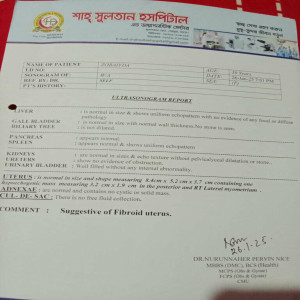

#250909G: জোবায়দা খাতুন দীর্ঘদিন ধরে জরায়ু টিউমারে ভুগছেন। গ্রাম: খন্দকার টোলা, জেলা: বগুড়া।